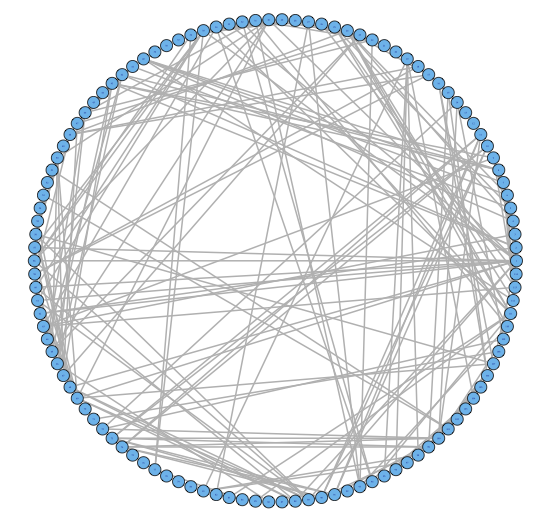

For our two-level problem (1.1.1), we must account for two sources of network variability when conducting population inference: (i) variability between subjects within a group and (ii) variability of the network selection procedure within a single subject. To see this, let us study a real multi-subject fMRI example. In Figure 2, we show estimated functional brain networks for subjects from the UCLA fMRI ABIDE data set INDI (2013). We describe the details of this data set, our pre-processing, and brain parcellation later in the Case Study in Section 5. In the top and middle panels, we estimate brain networks for each subject using graph selection methods for Gaussian graphical models (see Section 3.1 for details) and plot these as circle graphs to easily visualize network differences. It is clear that there are not only differences between autistic subjects and control subjects, but there is also large heterogeneity across subjects within each group. This is well-known in the neuroimaging literature (Milham et al., 2012; Nielsen et al., 2013), and makes finding statistically significant differences between subject groups much more challenging.

Less well studied in neuroimaging, is the second source of variability which arises from estimating networks for each subject instead of directly observing the networks. In the bottom panel of Figure 2, we re-estimate brain networks for a single control subject with bootstrap resampled data. It is clear that there is major intra-subject variability arising from our graph selection procedure. Indeed in neuroimaging, test–re-test studies which conduct brain imaging on the same subject in repeated sessions have shown high variability in the subject’s estimated brain networks (Wang et al., 2011). This also motivates the necessity of using a two-level model like (1.1.1) for population network inference as opposed to the one-level model and test statistics of the standard procedure.